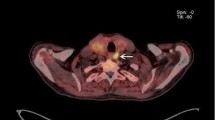

Right inferior parathyroid gland depicted by 11C-methionine (patient 6, hypercalcaemic hyperparathyroidism; Table 1). Upper left, CT scan; upper right, 11C-methionine PET scan [SUV(parathyroid tissue/cervical soft tissue)=2.2]; lower left, 11C-methionine PET/CT fusion image; lower right, right sagittal 11C-methionine PET scan of the neck

Among the 18 patients, high-resolution ultrasound identified two enlarged parathyroid glands in 11, three glands in six and four enlarged glands in one (Table 1). In ten of the 18 patients (55.5%), PET/CT demonstrated abnormal accumulation of 11C-methionine (one parathyroid gland in eight patients and two glands in two patients) (Table 1). Mean SUV(parathyroid tissue/cervical soft tissue) was 3.3 (range 2.1–4.9) and mean SUV(parathyroid tissue/thyroid tissue) was 2.5 (range 1.5–3.6). There was no significant difference in parathyroid gland 11C-methionine SUVs between the group with normal or low calcium levels and the group with hypercalcaemic hyperparathyroidism. It is of note that in patients with normo- or hypocalcaemic hyperparathyroidism, 11C-methionine PET/CT identified one abnormal gland in only three of ten patients (30%), while in the group with hypercalcaemic hyperparathyroidism, seven of eight patients (87.5%) had abnormal 11C-methionine PET/CT (p<0.01 by χ2 test). Of the latter seven patients, five had one abnormal gland (Figs. 1, 2) and two, two abnormal glands on PET/CT. The significant difference observed in the rate of detection of abnormal parathyroid glands at 11C-methionine PET/CT in the group of normo- or hypocalcaemic patients versus the group of hypercalcaemic patients might be explained by the fact that in hypercalcaemic patients, that is patients more likely to be affected by tertiary hyperparathyroidism, autonomous parathyroid glands could be biologically more active in trapping 11C-methionine. Further, in four of the ten patients (40%) with abnormal 11C-methionine PET/CT scans (all of whom had hypercalcaemic hyperparathyroidism), the largest parathyroid gland seen on high-resolution ultrasound did not demonstrate the highest 11C-methionine avidity. Comparisons of SUV with serum calcium and parathyroid hormone levels and parathyroid gland weight by regression analysis did not reveal statistically significant differences. No patient had co-existing thyroid nodules in the present series.